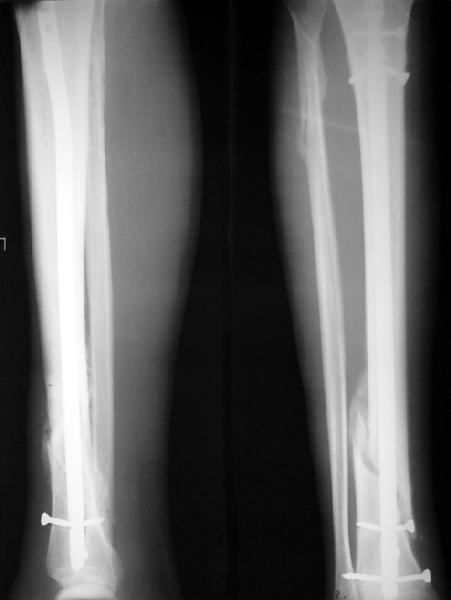

По крайней мере ходящих без дополнительной опоры через 1 месяц после операции с небольшой - при изолированной травме немало. Нестабильные по оси, кстати, не только оскольчатые, но и спиральные.

И если пациент еще не возвращается к полной нагрузке и функции, то не потому, что не разрешает врач, опасаясь несостоятельности фиксации.

Как мне показать пример? Фото стоящего на одной оперированной конечности пациента? O! Пример, подвигнувший нас на некоторое изменение технологий. Пациент этот ходил с полной нагрузкой вопреки рекомендациям. В качестве подтверждения - сломанный проксимальный статический винт к 1 мес., а к 2 мес. - все остальные. Сейчас мы перешли на более fool-proof остесинтез.

Ok. А также и следующий, в 3 месяца.

Это наглядная демонстрация возможности ранней полной нагрузки при нестабильном по оси повреждении, причем не в самых благоприятных механических условиях - при плохом сопоставлении, со слабым фиксатором.

Сверху - один статический винт, а снизу - три. Что раньше сломается? Конечно, он потом и нижние сломал, и Вы правы, если бы верхний динамичесий винт уже уперся бы в нижний край отверстия, будь гвоздь подлинее, перфорировал бы сустав как пить дать.

Как я уже говорил, мы сделали выводы из этого и других подобных случаев. Очевидно, решений проблемы два - либо уменьшить нагрузку, либо увеличить прочность фиксатора. Первое решение работает не со всеми больными, так что пошли по второму пути - мы больше не используем гвозди с запирающими винтами диаметром 4 мм.